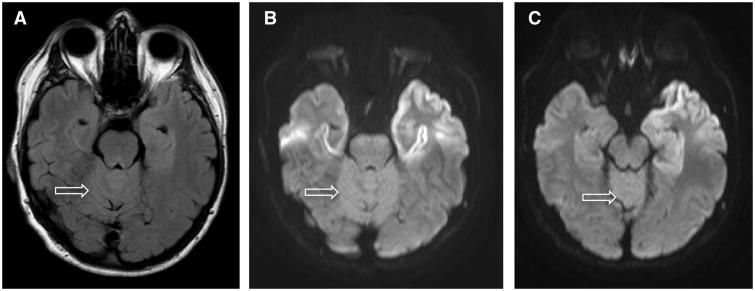

Patients with iatrogenic Creutzfeldt-Jakob disease due to administration of cadaver-sourced growth hormone during childhood are still being seen in the UK 30 years after cessation of this treatment. Of the 77 patients who have developed iatrogenic Creutzfeldt-Jakob disease, 56 have been genotyped. There has been a marked change in genotype profile at polymorphic codon 129 of the prion protein gene (PRNP) from predominantly valine homozygous to a mixed picture of methionine homozygous and methionine-valine heterozygous over time. The incubation period of iatrogenic Creutzfeldt-Jakob disease is significantly different between all three genotypes. This experience is a striking contrast with that in France and the USA, which may relate to contamination of different growth hormone batches with different strains of human prions. We describe the clinical, imaging, molecular and autopsy features in 22 of 24 patients who have developed iatrogenic Creutzfeldt-Jakob disease in the UK since 2003. Mean age at onset of symptoms was 42.7 years. Gait ataxia and lower limb dysaesthesiae were the most frequent presenting symptoms. All had cerebellar signs, and the majority had myoclonus and lower limb pyramidal signs, with relatively preserved cognitive function, when first seen. There was a progressive decline in neurological and cognitive function leading to death after 5-32 (mean 14) months. Despite incubation periods approaching 40 years, the clinical duration in methionine homozygote patients appeared to be shorter than that seen in heterozygote patients. MRI showed restricted diffusion in the basal ganglia, thalamus, hippocampus, frontal and the paracentral motor cortex and cerebellar vermis. The electroencephalogram was abnormal in 15 patients and cerebrospinal fluid 14-3-3 protein was positive in half the patients. Neuropathological examination was conducted in nine patients. All but one showed synaptic prion deposition with numerous kuru type plaques in the basal ganglia, anterior frontal and parietal cortex, thalamus, basal ganglia and cerebellum. The patient with the shortest clinical duration had an atypical synaptic deposition of abnormal prion protein and no kuru plaques. Taken together, these data provide a remarkable example of the interplay between the strain of the pathogen and host prion protein genotype. Based on extensive modelling of human prion transmission barriers in transgenic mice expressing human prion protein on a mouse prion protein null background, the temporal distribution of codon 129 genotypes within the cohort of patients with iatrogenic Creutzfeldt-Jakob disease in the UK suggests that there was a point source of infecting prion contamination of growth hormone derived from a patient with Creutzfeldt-Jakob disease expressing prion protein valine 129.